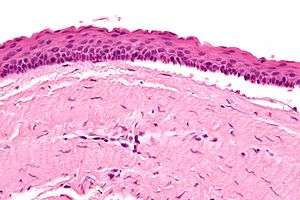

The definitive diagnosis is by histologic analysis, i.e. excision and examination under the microscope.

Under the microscope, KCOTs vaguely resemble keratinized squamous epithelium;[3] however, they lack rete ridges and often have an artifactual separation from their basement membrane.

Intermed. mag.